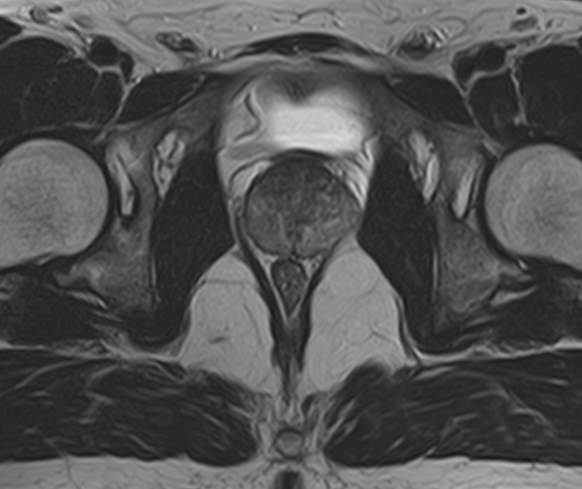

Простата расположена в труднодоступной для диагностики анатомической области, однако метод магнитно-резонансной томографии позволяет детально изучить структуру органа и окружающих ее тканей, включая семенные пузырьки (секреторные органы, вырабатывающие жидкую часть семенной жидкости) и семявыносящие протоки.

В клинике «Доступная медицина» диагностика заболеваний предстательной железы на экспертном уровне выполняется при помощи современного высокопольного магнитно-резонансного томографа TOSHIBA VANTAGE TITAN 1,5 Тесла. Аппарат производит сканирование в виде послойных тонких срезов с шагом от 1 мм и преобразует их при помощи новейших цифровых программ в изображения трехмерного формата. Методика позволяет получить максимально полную картину о состоянии структуры простаты и окружающих тканей и поставить точный диагноз.